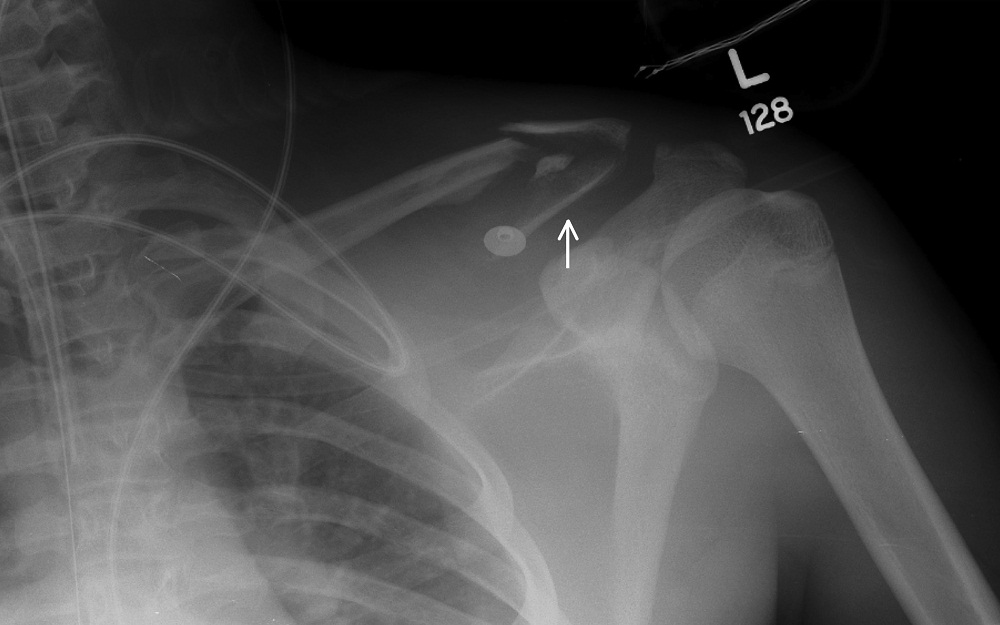

Fractures that involve the portion of the clavicle lateral to the CCL correspond to Group II fractures [2]. Dr. Neer further divided these into subtypes that factor in the acromioclavicular joint integrity and CCL attachments [9]. Type 1 fractures occur in between the conoid and trapezoid ligaments of the CCL, and remain attached to the medial and lateral fragments, respectively. There is usually minimal to no displacement (Figure 10 and 11). Type 2 fractures are medial to the CCL attachment, and this medial fragment separates from the CCL. This type is further divided into the subtypes 2A and 2B. The conoid and trapezoid ligaments remain attached to the distal fragment in type 2A (Figure 12 and 13), while the conoid is detached from the proximal fragment and the trapezoid remains attached to the distal fragment in type 2B (Figure 14 and 15). Type 3 involves intra-articular extension (Figure 16 and 17 ). Type 4 is a periosteal sleeve avulsion from the inferior cortex while attached to the coracoclavicular ligament, wherein the medial fragment is often displaced superiorly (Figure 18 and 19). Type 5 also involves an avulsion of the CCL (Figure 20 and Figure 21) [10].